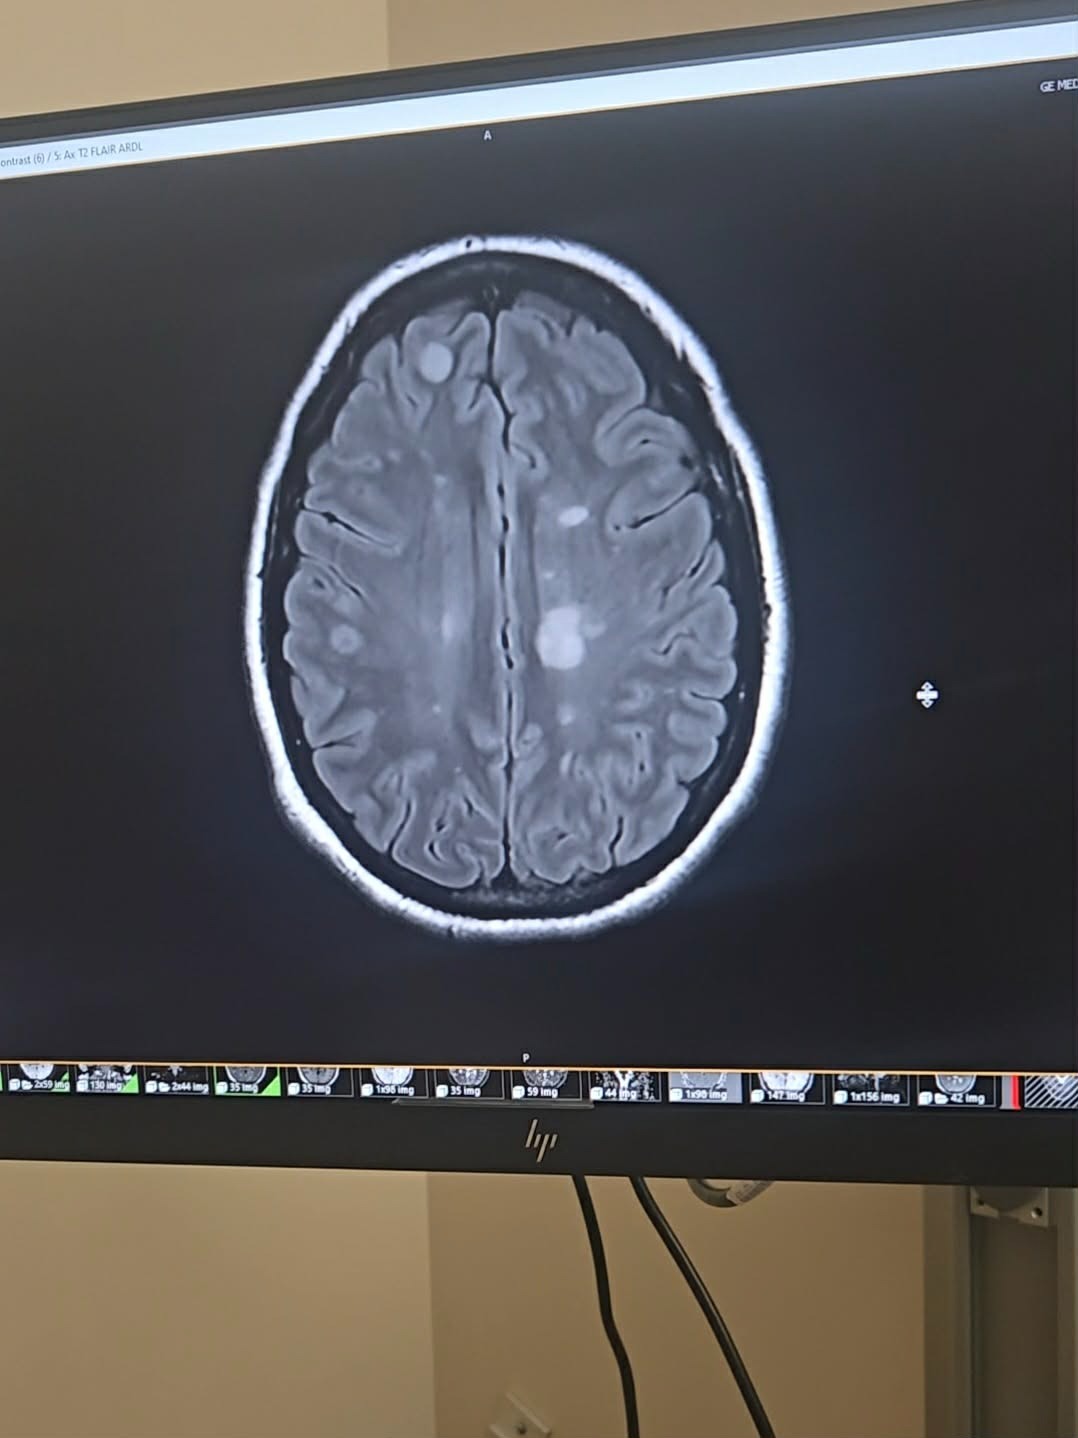

Over the past year, Annie’s life has been upended in ways no one should ever have to experience. She was diagnosed with aggressive Multiple Sclerosis (MS) after struggling with vision problems and strange neurological symptoms. Since then, her disease has moved at a frightening pace, bringing relapses, new brain lesions, and numbness that spreads across the right side of her body. Each flare leaves her physically weaker, emotionally drained, and wondering what new challenges tomorrow will bring.